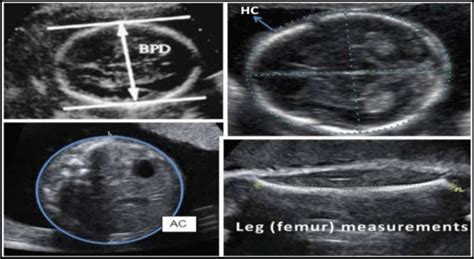

• BPD (Biparietal Diameter): This measures the diameter of your baby’s head from one side to the other. Think of it as the width of their head. This measurement is super important because it helps estimate the baby’s gestational age and growth.

• HC (Head Circumference): This is the measurement of the circumference around your baby’s head. It’s like measuring the hat size of your little one. HC is another key indicator of growth and development.

• AC (Abdominal Circumference): As you might have guessed, this measures the circumference of your baby’s abdomen (tummy). It helps assess the baby’s weight and overall growth, and it’s particularly sensitive to factors like nutrition.

• FL (Femur Length): This measures the length of your baby’s femur, which is the thigh bone. The femur is one of the longest bones in the body, and its length is a useful indicator of the baby’s overall skeletal development and size.